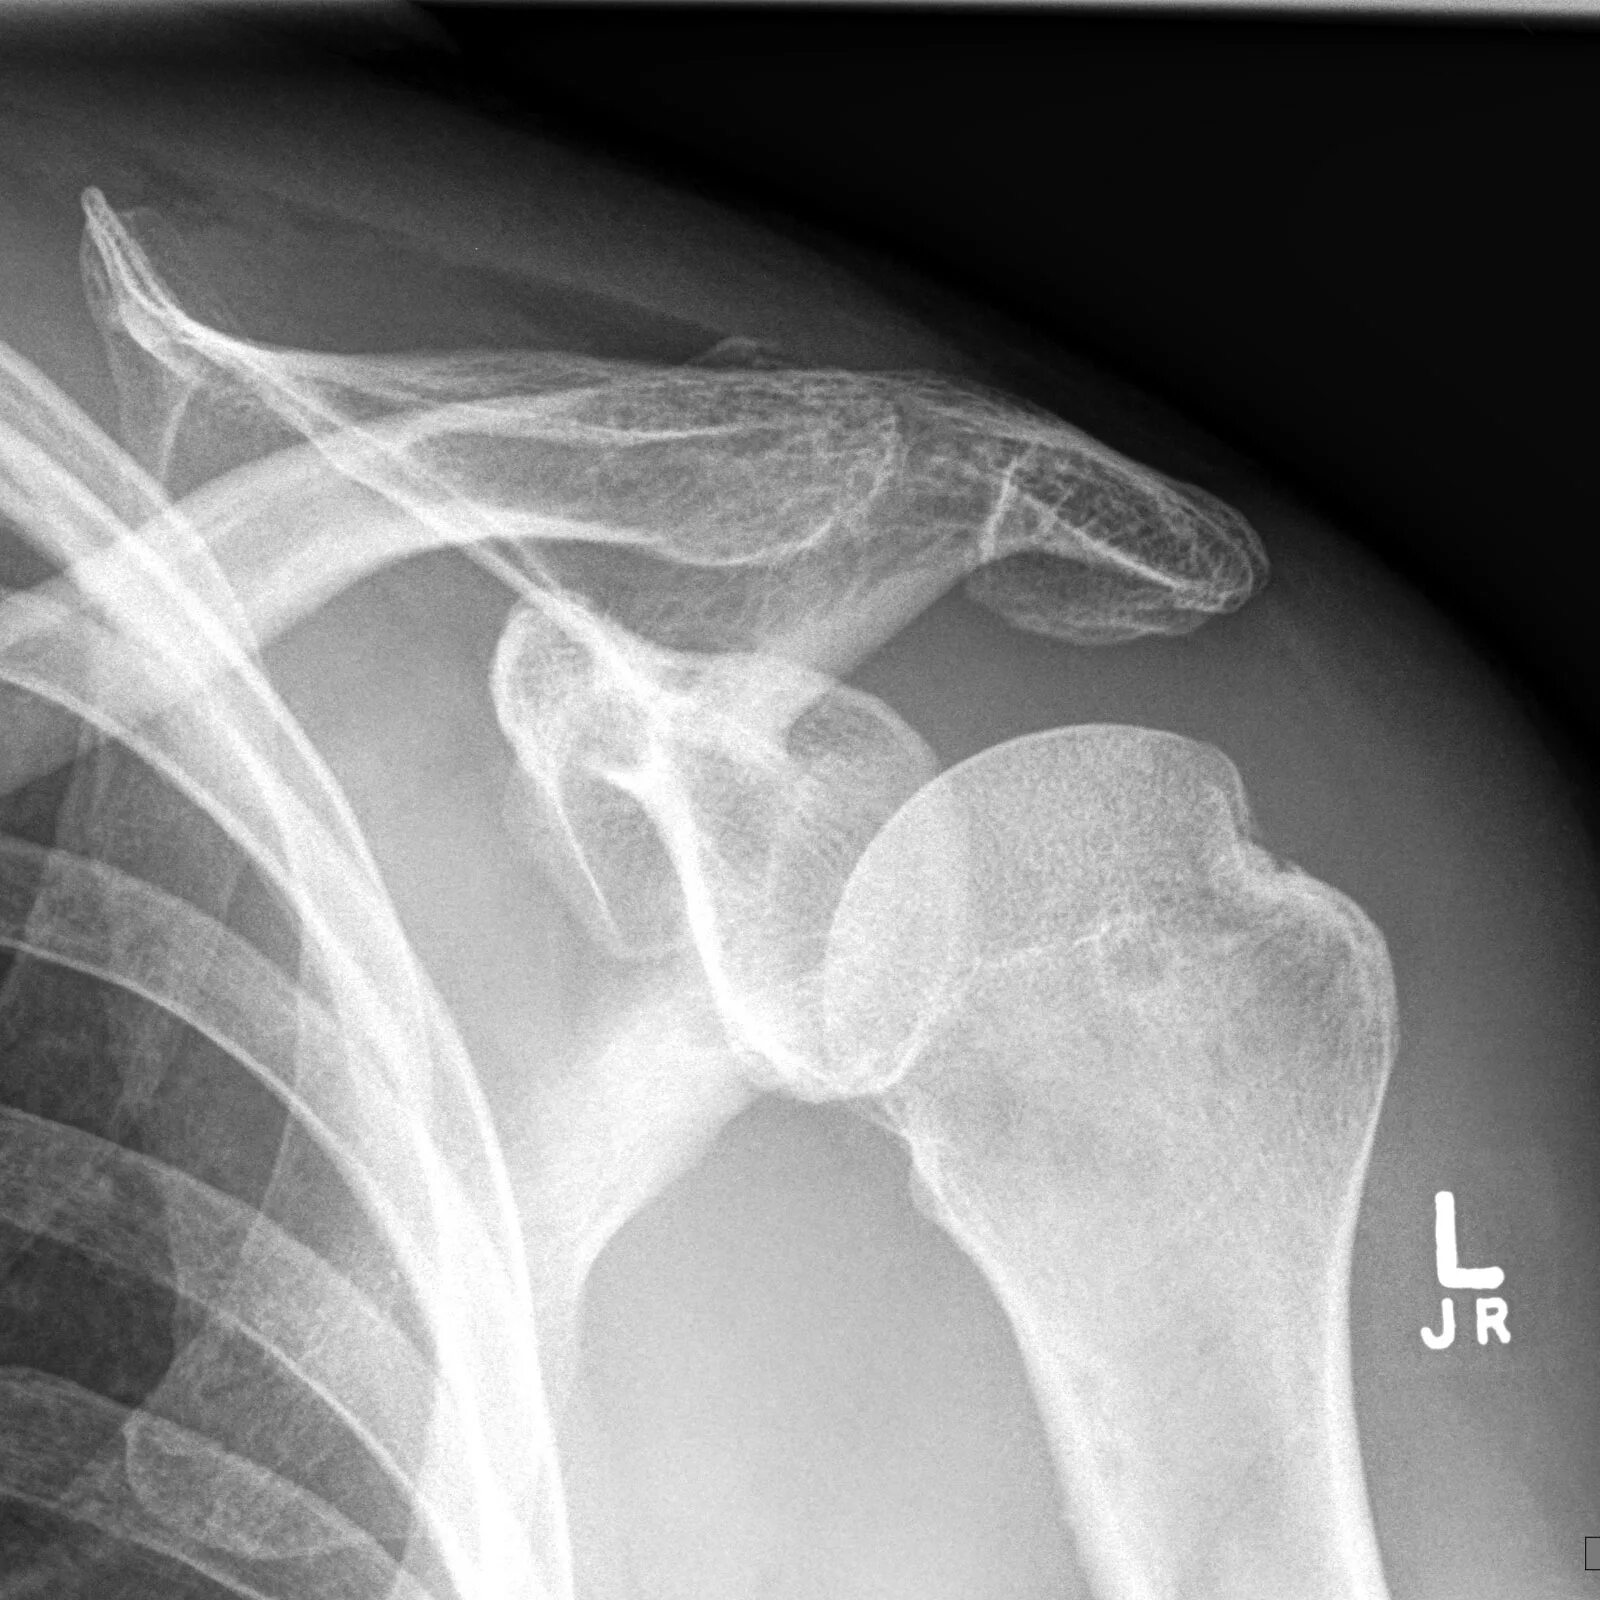

Вывих плеча у пожилых